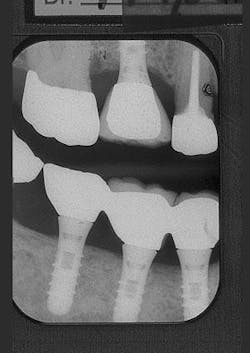

Figure 5 - Placement of three ITI implants

Figure 6 - Same patient with hopeless Tooth No. 3

Figure 7 - Extraction Tooth No. 3 / Perioglas graft

Figure 8 - Healed bone graft Tooth No. 3

Figure 9 - ITI implant placement Tooth No. 3

Figure 10 - Restored implants